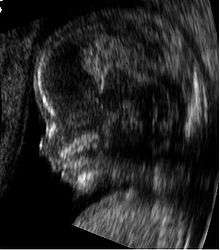

Medical sonography (ultrasonography) is an ultrasound-based diagnostic medical imaging technique used to visualize muscles, tendons, and many internal organs, to capture their size, structure and any pathological lesions with real time tomographic images. Ultrasound has been used by radiologists and sonographers to image the human body for at least 50 years and has become a widely used diagnostic tool. The technology is relatively inexpensive and portable, especially when compared with other techniques, such as magnetic resonance imaging (MRI) and computed tomography (CT). Ultrasound is also used to visualize fetuses during routine and emergency prenatal care. Such diagnostic applications used during pregnancy are referred to as obstetric sonography. As currently applied in the medical field, properly performed ultrasound poses no known risks to the patient.[23] Sonography does not use ionizing radiation, and the power levels used for imaging are too low to cause adverse heating or pressure effects in tissue. Although the long-term effects due to ultrasound exposure at diagnostic intensity are still unknown,[24] currently most doctors feel that the benefits to patients outweigh the risks.[25] The ALARA (As Low As Reasonably Achievable) principle has been advocated for an ultrasound examination – that is, keeping the scanning time and power settings as low as possible but consistent with diagnostic imaging – and that by that principle non-medical uses, which by definition are not necessary, are actively discouraged.[26]